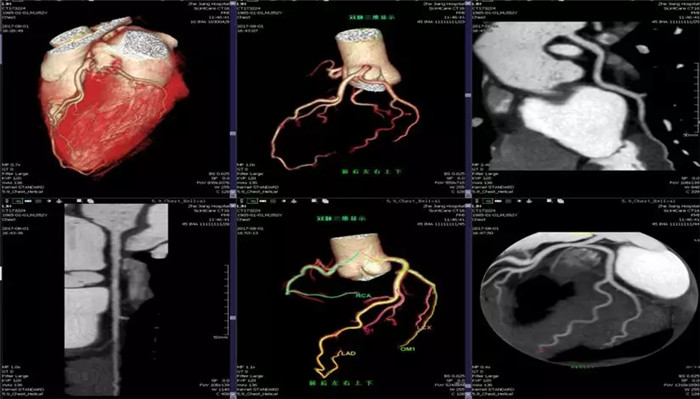

·心臟掃描應(yīng)用